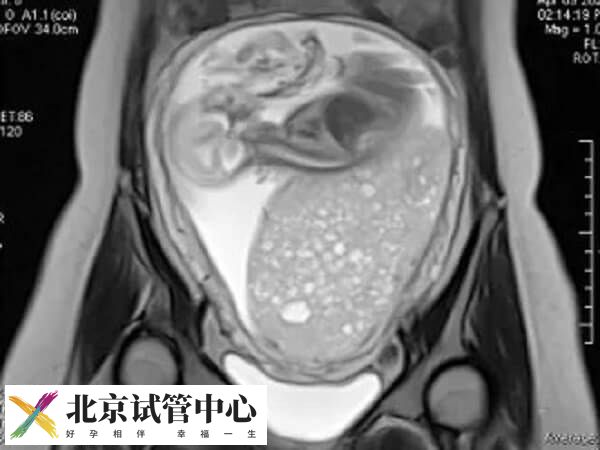

试管婴儿移植后,部分患者可能会出现一些特殊的妊娠并发症,比如葡萄胎,这是形状类似于葡萄样水泡样得名而来。一般葡萄胎常见于早期妊娠,其病因尚未完全明确。但根据医学研究,一般认为葡萄胎多数情况下是由染色体异常引起的,其中男方和女方都有可能存在异常。